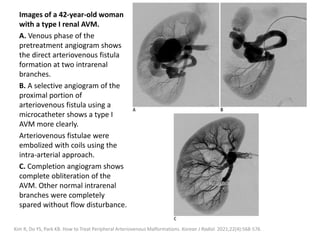

Although this new entity shares some similarities

with the more common intra-muscular VMs, it is

important to recognize FAVA because of a

different management approach.

Alomari AI, Spencer SA, Arnold RW, Chaudry G, Kasser JR, Burrows PE, et al. Fibro-adipose vascular anomaly: clinical-radiologic-

pathologic features of a newly delineated disorder of the extremity. J Pediatr Orthop. 2014;34: 109-17.

Amarneh M, Shaikh R. Clinical and imaging features in fibro-adipose vascular anomaly (FAVA). Pediatr Radiol. 2020;50(3):380-387.

Clinical presentation

Patients present with complex symptoms

including persistent pain, discomfort,

functional impairment and contracture.

The clinical and imaging features can be

confusing and often overlap with those of

other vascular malformations and tumors.